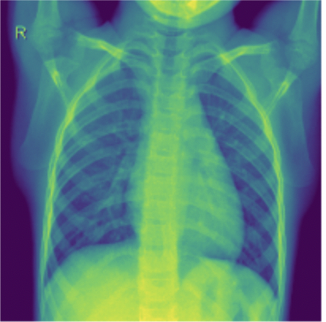

Pneumonia is an acute pulmonary infection which causes inflammation of air sacs called Alveoli. It is most common in underdeveloped or developing nations which have below average air quality and sanitation standards. Pneumonia can be of these three forms viral, bacterial or fungal which makes it airborne and contagious. It mostly effects children under the age of five or elderly people who have weak immune system [2]. Symptoms include coughing, fever, difficulty in breathing, loss of appetite etc. and is life threatening. COVID-19 induced Pneumonia has been a major reason for pandemic deaths in the world [3]. Pneumonia is a rapid attacking infection whose quick diagnosis is important for saving lives. Detection of Pneumonia normally requires a highly skilled doctor to look at the Chest X-rays (CXR) and CT scans and requires medical history to arrive at a conclusion. Normally a foggy CXR with white spots are a few indicators of Pneumonia Fig. 1. This manual process might be expensive and critically time consuming. The recent advancements in Machine learning and Computer vision might prove really helpful in quick and accurate detection of Pneumonia and can potentially save a lot more lives especially during pandemics like COVID-19 which faced shortage of human expertise.